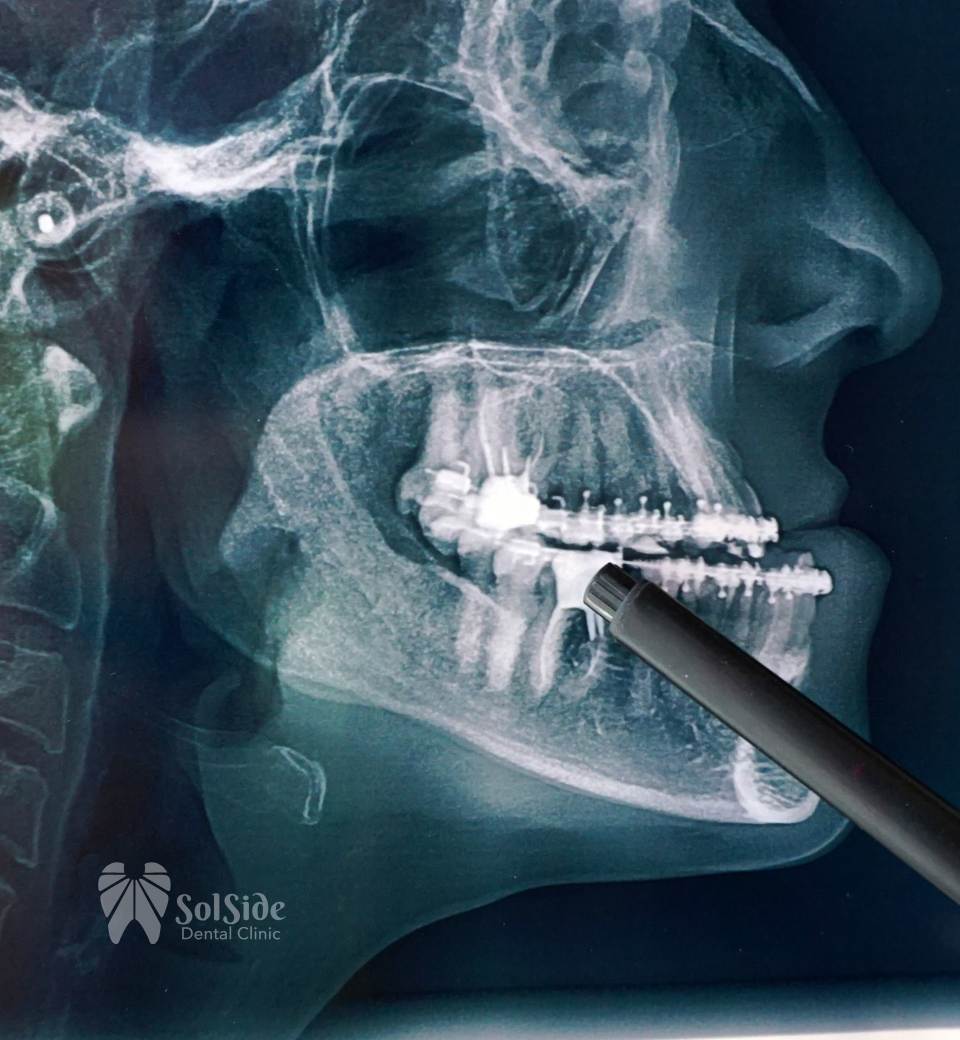

Orthognathic & Maxillofacial Surgery

At SolSide Dental Clinic, our specialists perform precise orthognathic and maxillofacial surgeries to correct jaw misalignments, improve chewing function, and enhance facial aesthetics. With advanced digital planning and 3D imaging, we ensure accuracy, safety, and predictable results.